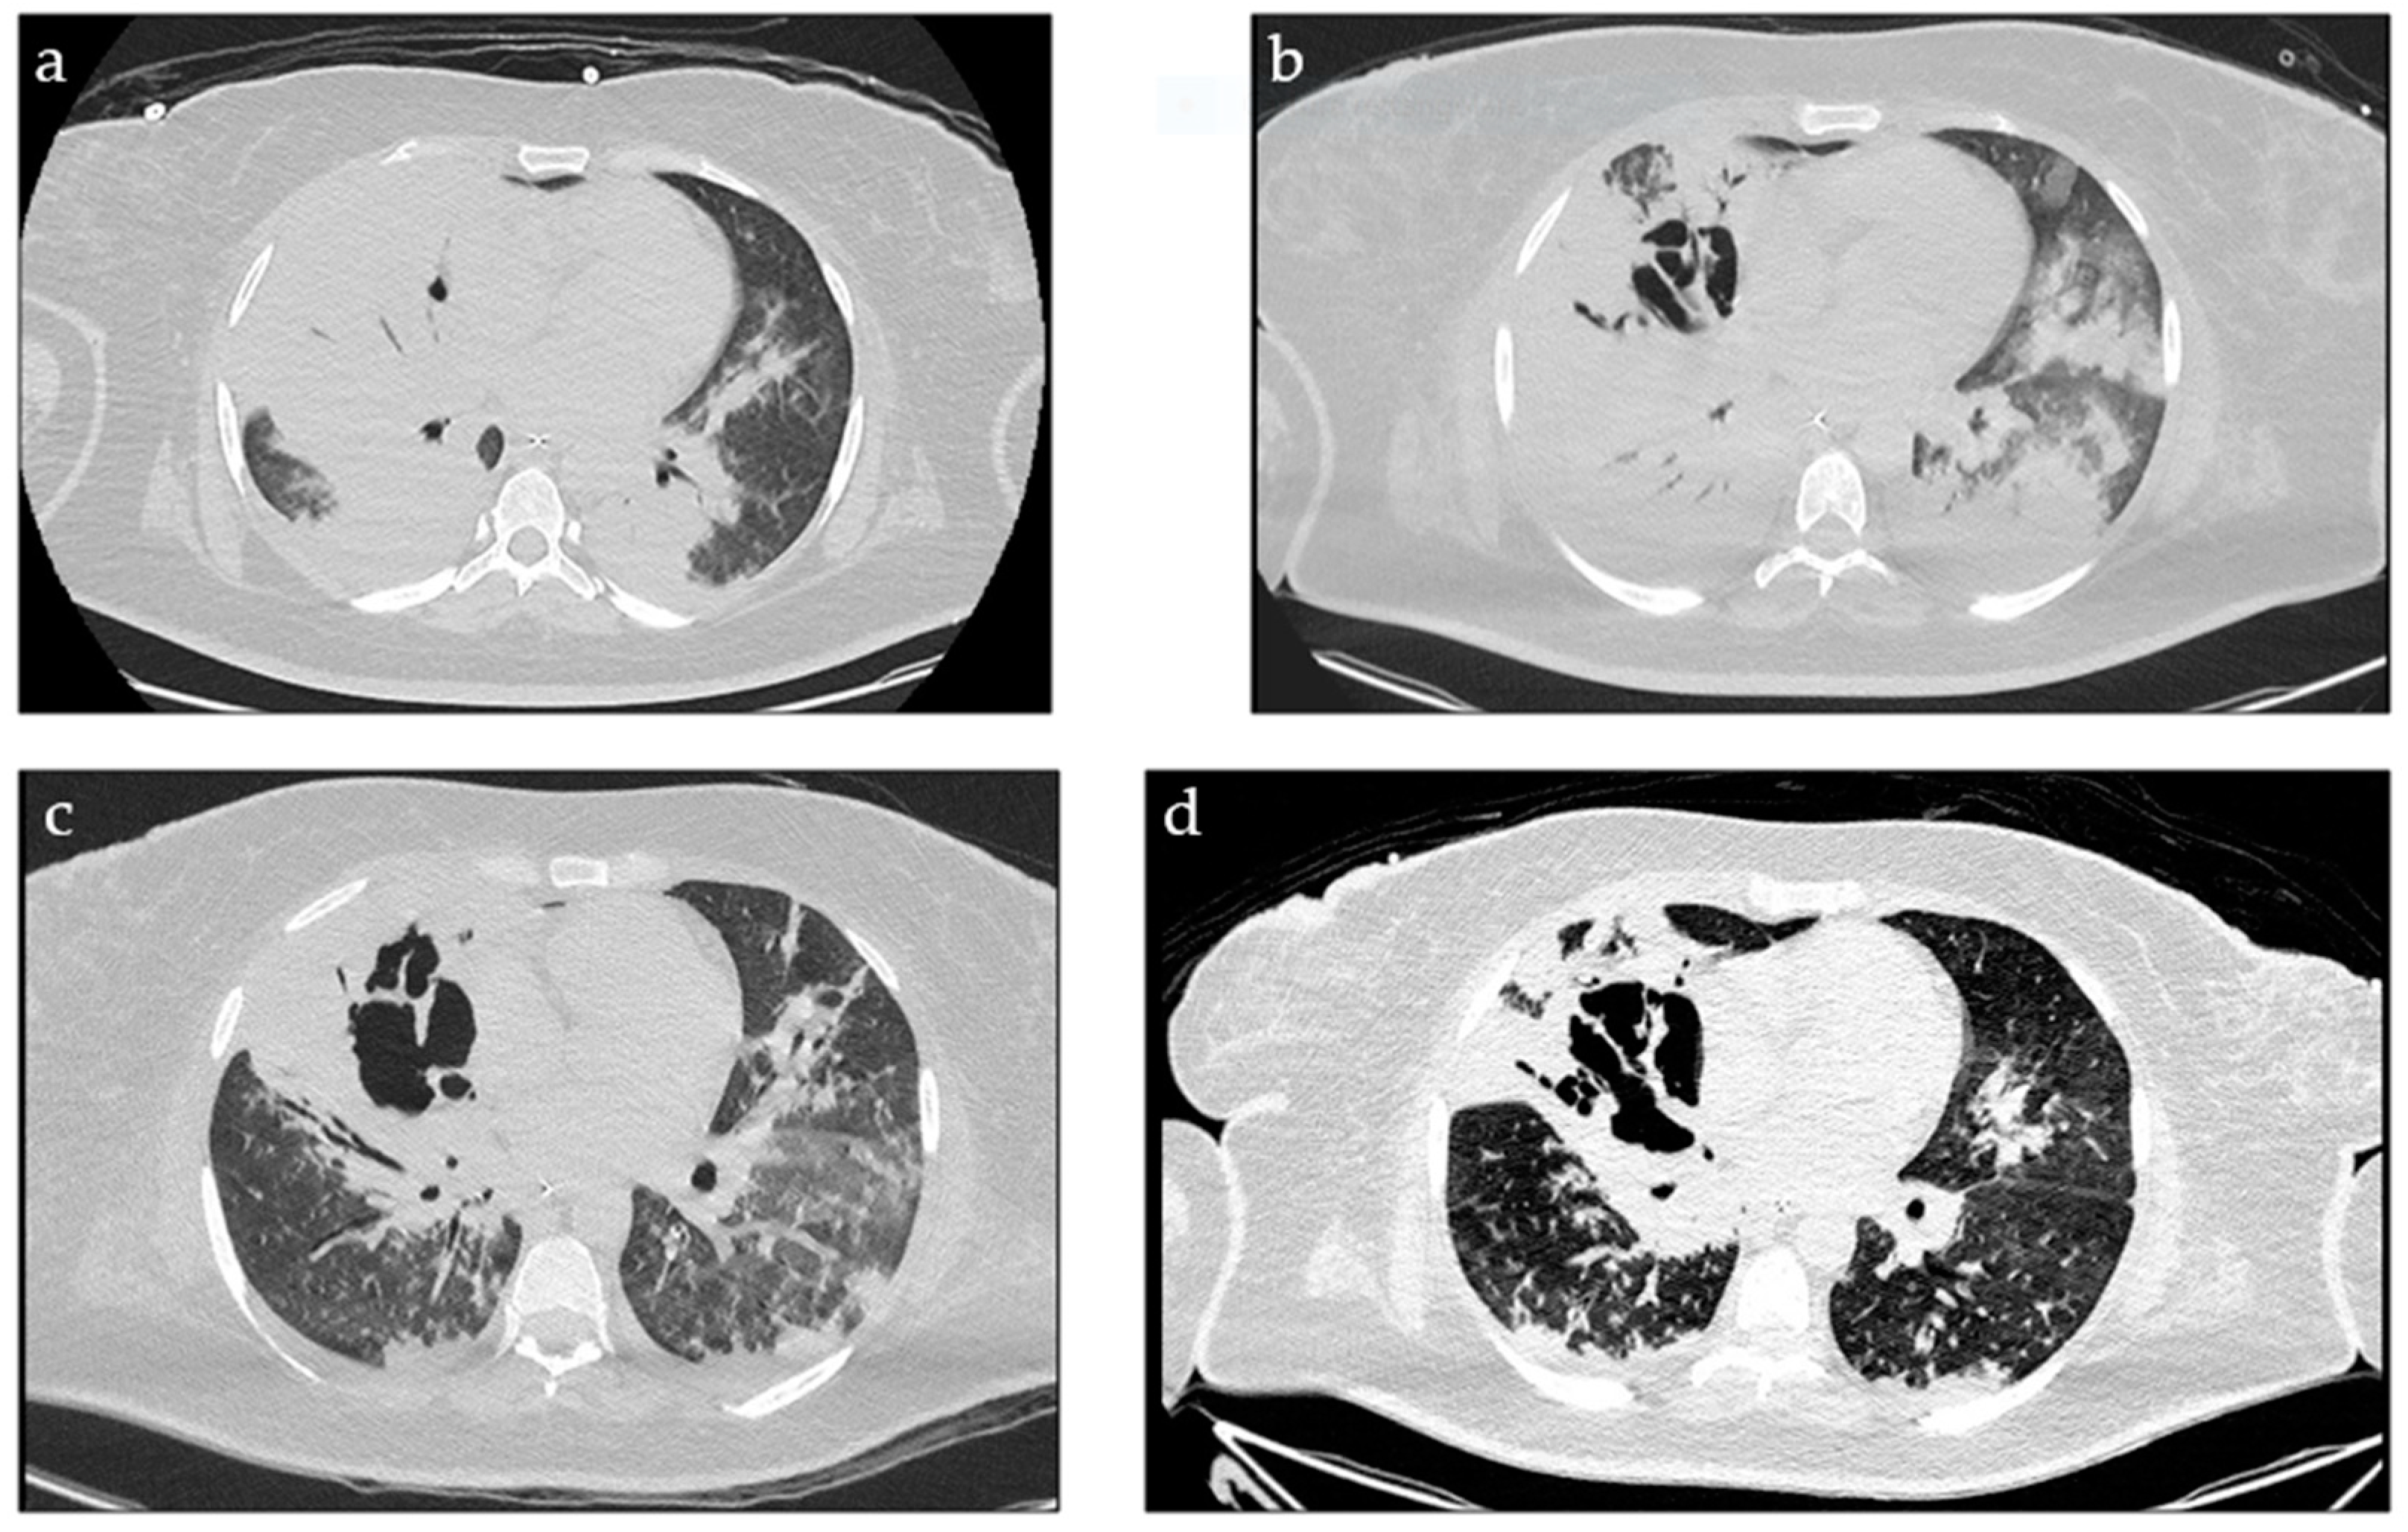

2. Case Report